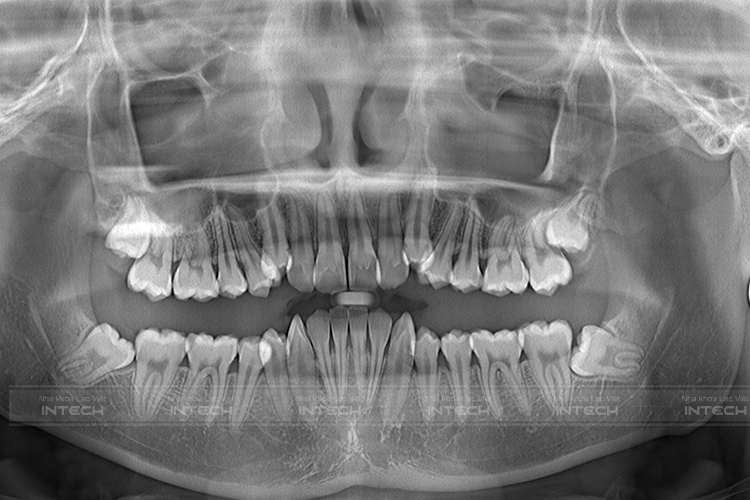

Qua kết quả chụp phim, thăm khám tình trạng ban đầu của khách hàng Trần Văn Đông, đội ngũ chuyên gia chỉnh nha với hơn 1000 ca lâm sàng thành công tại Lạc Việt Intech đã đưa ra chẩn đoán tình trạng cụ thể của Đông như sau:

• Răng chen chúc, khấp khểnh

• Khớp cắn ngược

• Góc nghiêng thấy rõ tình trạng móm

Kế quả chụp phim CT Conebeam của Đông tại Lạc Việt Intech